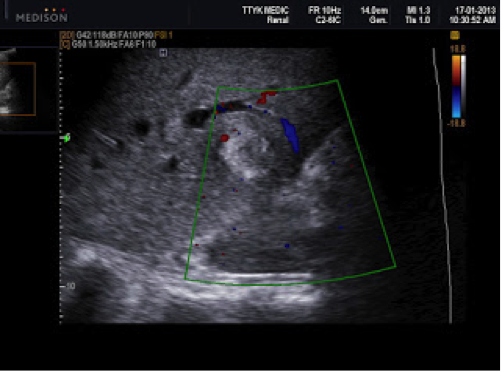

Bệnh nhân nữ 24 tuổi, chậm kinh 2 tuần, nghi có thai nhưng siêu âm tử cung không thấy túi thai trong tử cung hoặc khối cạnh tử cung.

Siêu âm phát hiện ở gan có ổ tròn đậm âm, kích thước 1,86cm, ở giữa có dịch.

Xét nghiệm β-hCG: 34.000 IU/L.

CT: có một ổ trong gan gần túi mật kích thước 2cm, ở giữa khối có dịch (giảm âm), được cung cấp máu từ động mạch gan.

Chẩn đoán thai dưới gan. Điều trị tiêm MTX, sau 2 tuần, xét nghiệm β-hCG trở về bình thường, không cần can thiệp ngoại khoa. Kết quả tốt do phát hiện sớm (Phan Thanh Hải và cs., 2007).